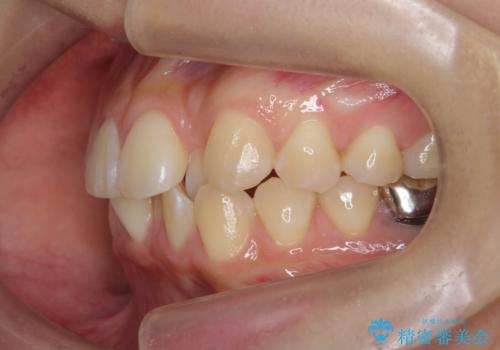

- 噛んだ時の前歯正中のズレ、引っ込んでいる前歯を治したい。と矯正治療を希望され来院されました。

左上2の前歯はスペースが足りないため、後方に引っ込んでしまっている状態です。